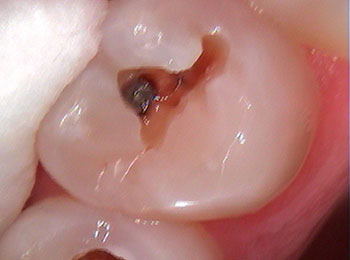

While silver/amalgam fillings are a safe, long-lasting, and trusted dental material — tooth-colored/metal free fillings can provide a strong esthetic alternative. These composite resin fillings are bonded to tooth structure allowing minimal removal of tooth structure making them a very conservative restoration. Materials come in a wide variety of shades to ensure proper color matching and is therefore visually undetectable.

Before decay removal

After decay removal